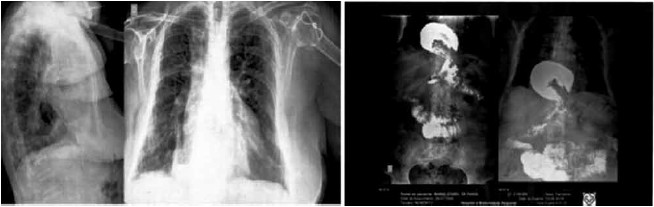

Mulher, 68 anos, com dispneia, fadiga, dor retroesternal, vômitos e refluxo gastroesofágico há dois anos, apresentou piora clínica com disfagia a líquidos, não tolerando decúbito para dormir nos últimos meses. Portadora de hipotireoidismo e hipertensão arterial controlados. Na investigação diagnóstica, foi realizada radiografia do tórax, que apresentou imagem retrocardíaca irregular. Posteriormente, prosseguiu-se a investigação com seriografia contrastada do esôfago-estômago-duodeno (imagens a seguir).

(Arquivo pessoal; imagens usadas com autorização)